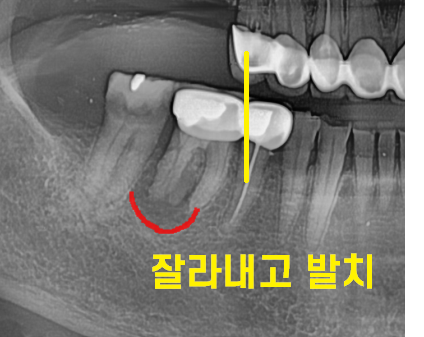

230526

오른쪽 위에 어금니는 치아가 없고

아래 어금니의 경우 염증으로 잇몸 뼈가 녹아있었는데요.

아래 치아의 경우 문제가 되는 부분만 1)임플란트를 한다.

- 브릿지 치료를 한다

2개의 선택지가 있었습니다.

각각의 장단점을 설명드렸고

브릿지 치료로 진행하기로 하였습니다.

문제가 되는 치아와 앞에 치아가 묶여 있어

잘라내서 새로 씌워줘야하고

맨 끝에 치아도 치료 후 보철이 필요하다보니

브릿지로 3개 한번에 씌우는 것을

선택해주셨습니다.